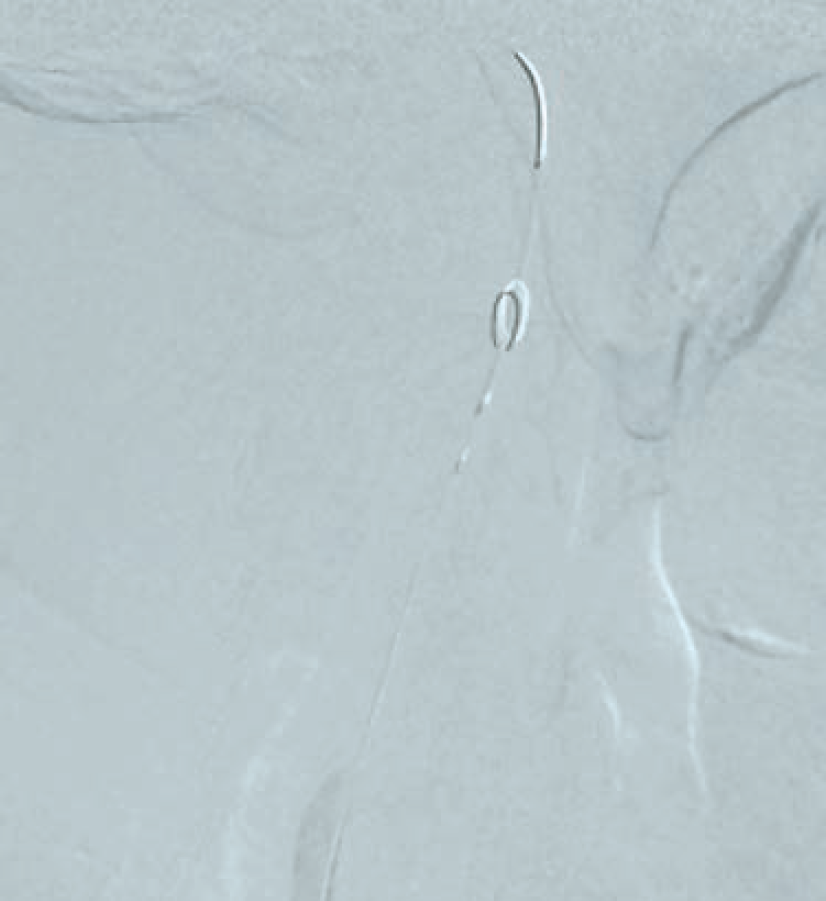

Following aseptic measures and under local anesthesia, a 7 French (Fr) right femoral access was obtained using a routine-length sheath. An .035-inch J-tip guide wire was then parked at the right common carotid artery (RCCA) using a 5 Fr Judkins right catheter, exchanged by a 7 Fr multipurpose guide. This was followed by advancement of a FilterWire EZ (Boston Scientific) across the ostial internal carotid artery stenosis, and deployed in the distal part of the extracranial ICA (Figure 2). After deployment of the FilterWire EZ, a direct stenting strategy was adopted to minimize thromboembolization. A 6 mm x 40 mm self-expanding stent was deployed at the RICA ostium (Figure 3). To our surprise, the view after stent placement showed zero flow into the distal RICA. (Figure 4) The reason appeared to be choking of the filter due to thromboembolization. The filter appeared to be overwhelmed by the volume of the debris captured. A 6 Fr Export catheter (Medtronic) was employed to suction debris from the distal ICA (Figure 5). We also administered pharmacotherapy using intra-arterial nitrate boluses and a weight-based tirofiban bolus. After these measures, there was fair flow into the distal ICA. During the period of no flow, the patient had transient hemispheric ischemic signs and an oropharyngeal airway was required, but his vitals remained stable. These symptoms rapidly resolved after establishment of ICA flow. After establishing blood flow, the proximal half of the stent that remained under-expanded was post dilated using a 4.5 mm noncompliant balloon at 12 atmospheres (Figure 6). Post dilatation, the angiographic view demonstrated good stent expansion and adequate distal flow (Figure 7). The distal protection device was then successfully removed using its retrieval sheath. The final DSA angiogram revealed excellent flow into the distal carotid (Figure 8A) and intracranial vasculature (Figure 8B), confirming no intracranial embolization. The guide was then safely removed over the .035-inch guide wire.